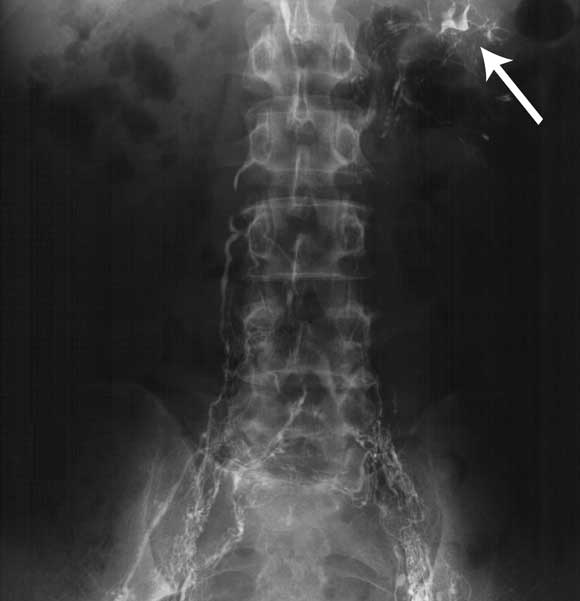

A chest x-ray and computed tomography scan of the abdomen and pelvis were normal. A biopsy of the right kidney showed evidence of mild mesangial change, consistent with diabetes mellitus. Lymphoscintigraphy showed delayed lymphatic transport, particularly on the left side, but no physical obstruction to lymphatic drainage. Contrast lymphangiography demonstrated a grossly abnormal lymphatic system in the pelvis and groin with a unilateral left-sided lymphorenal communication (Box 2).